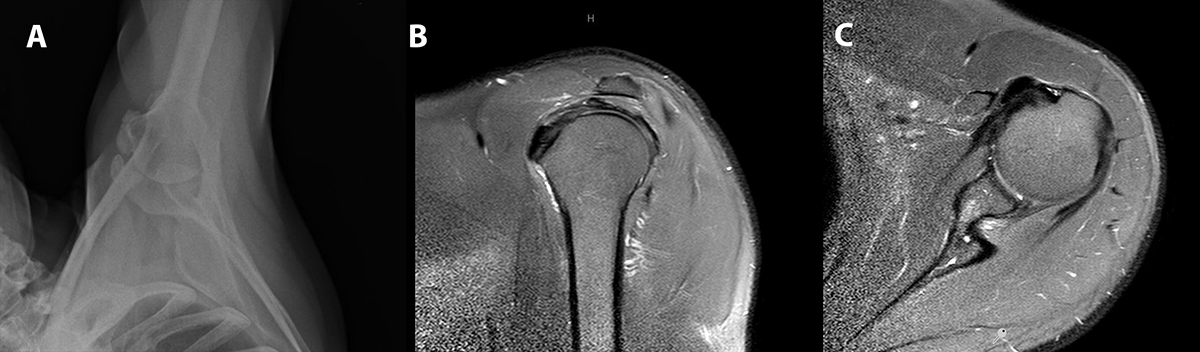

Las radiografías y la resonancia del hombro izquierdo preoperatorias mostraban una calcificación dentro del músculo subescapular (fig. 1 a-c). Luego de 2 meses de tratamiento conservador fallido que incluyó crioterapia, kinesiología y una infiltración con corticoides, se indicó la remoción artroscópica de la calcificación del subescapular.

Figura 1: A) Radiografía de hombro izquierdo preoperatoria en proyección axilar donde se observa la calcificación del subescapular. B y C ) Cortes sagital y axial respectivamente de la resonancia nuclear magnética preoperatoria demostrando el depósito de calcio por delante del tendón del subescapular.